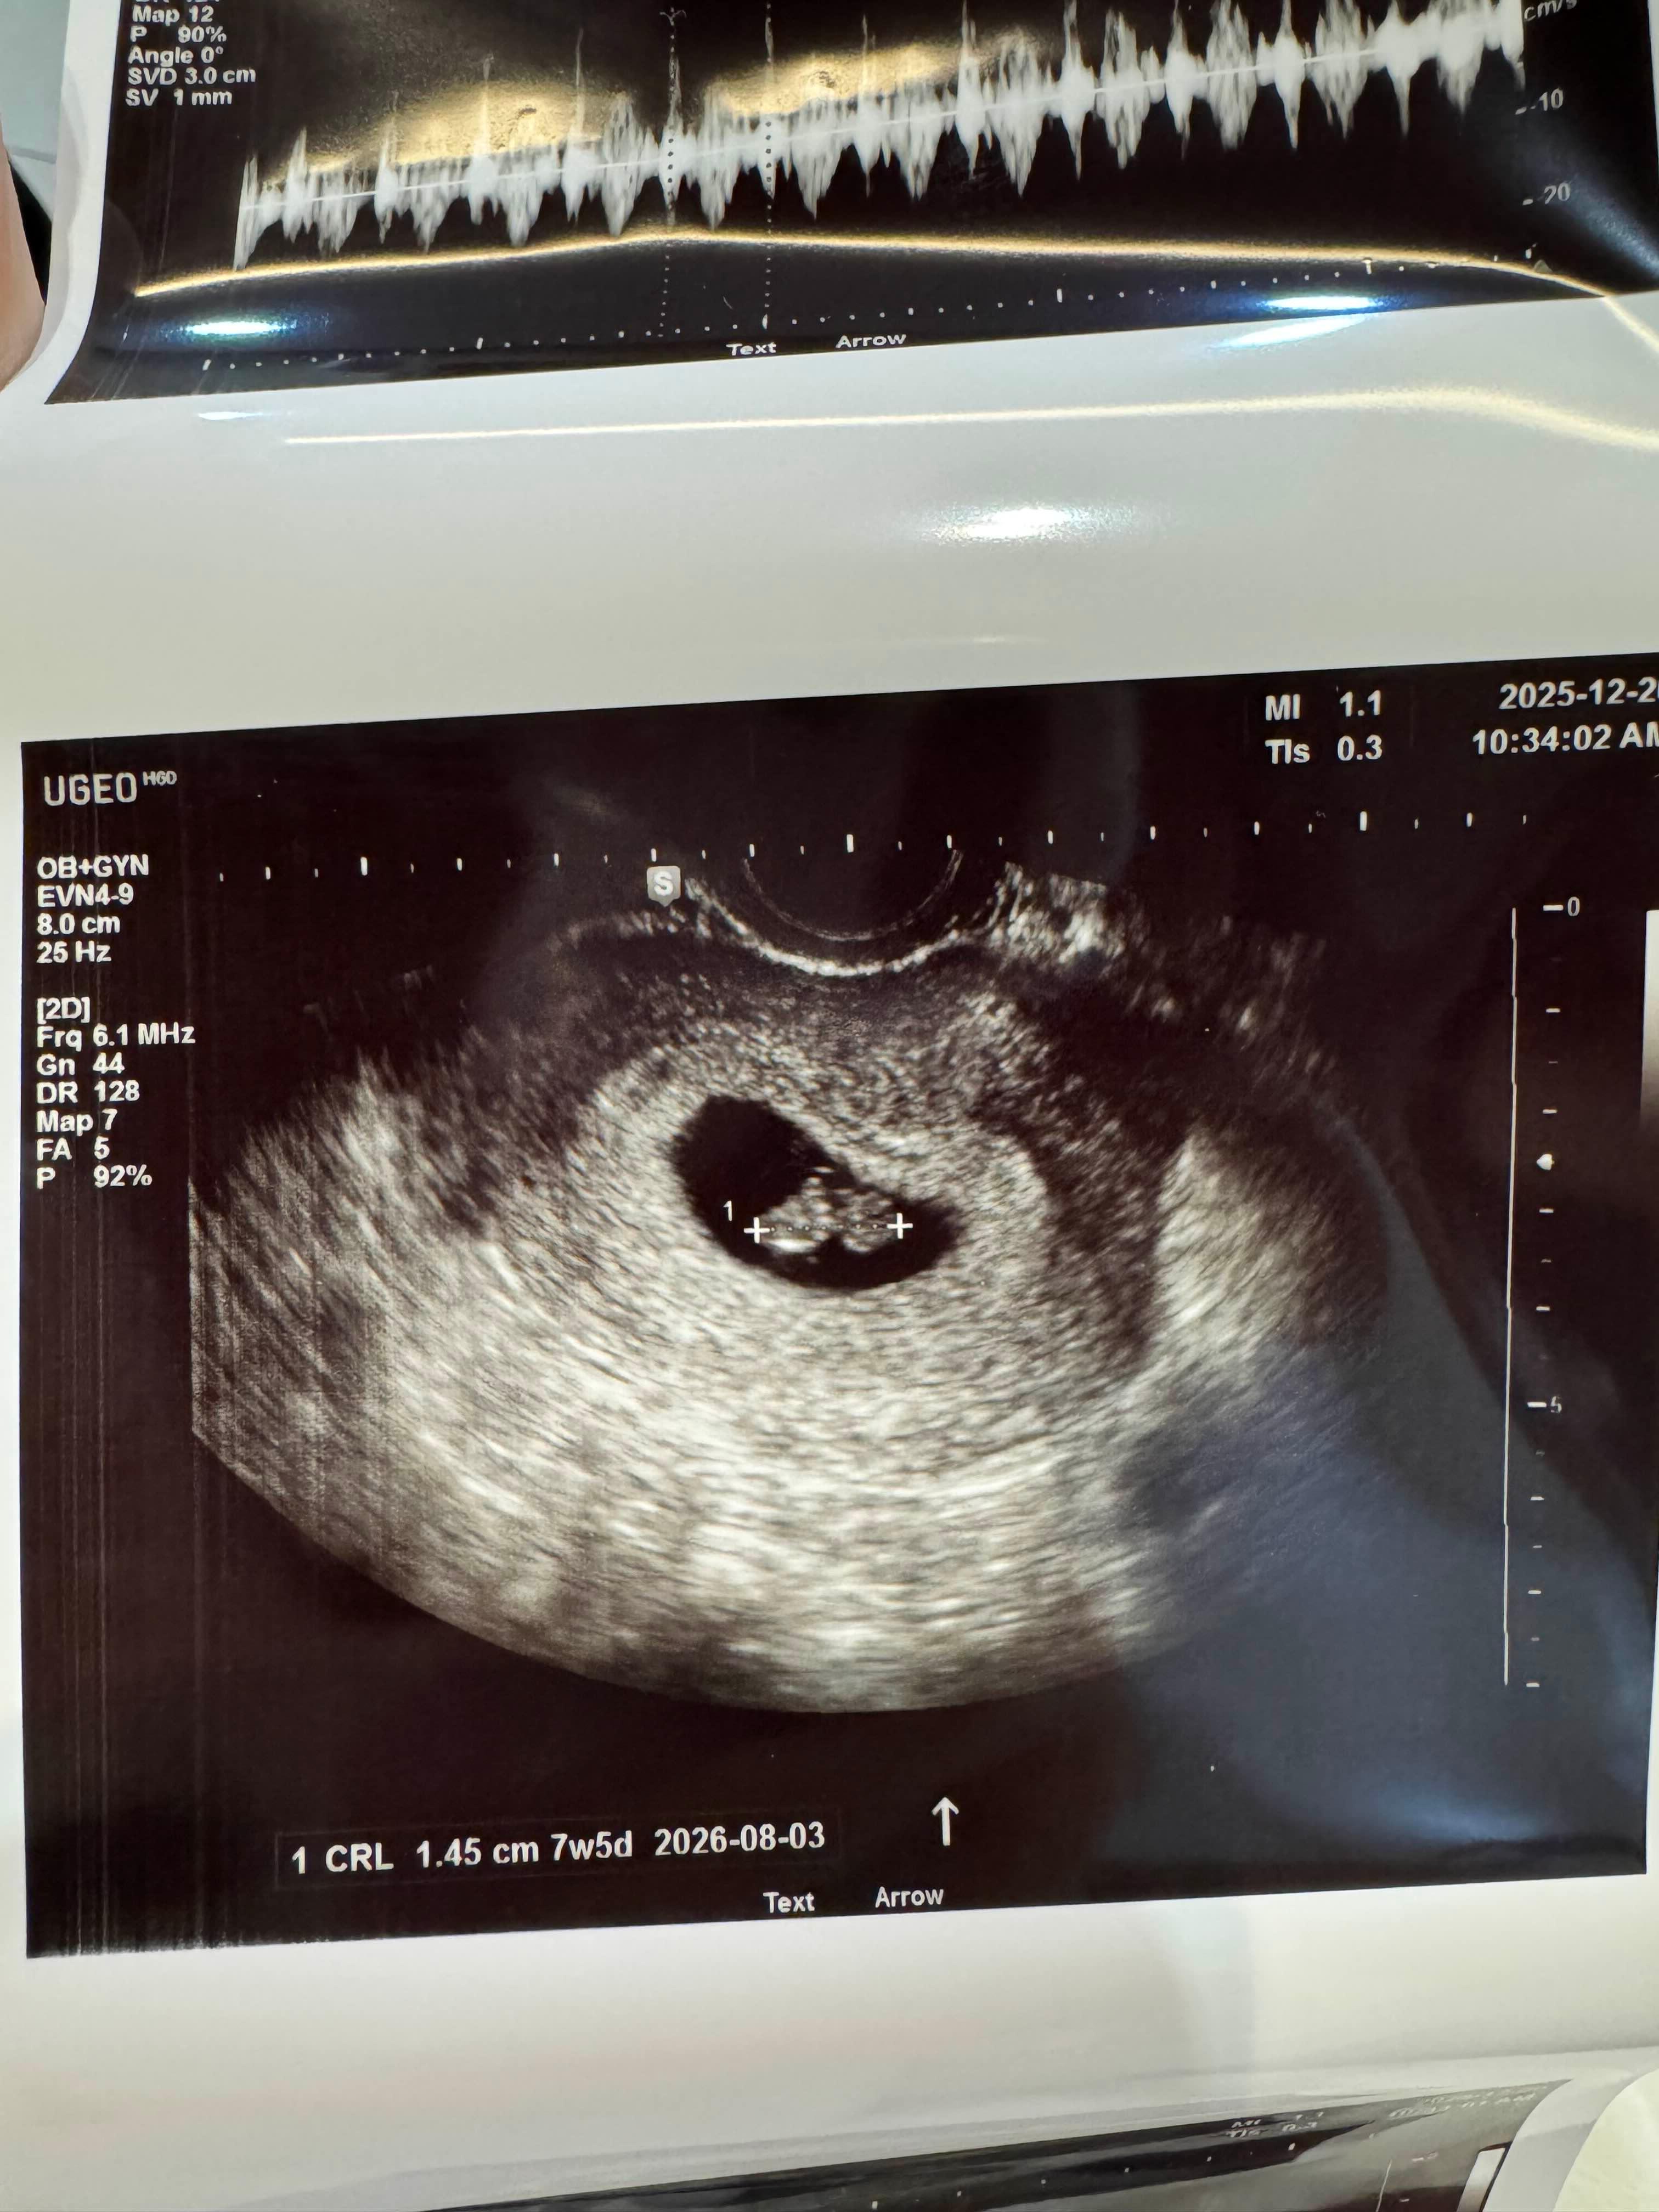

12월20일 아가가 잘있나 보러간날

1.45cm라니 너무 귀엽네요

지금 현재 1월23일인데 손발이 생기고

3cm이상으로 커있는 우리 깜짝이 ><